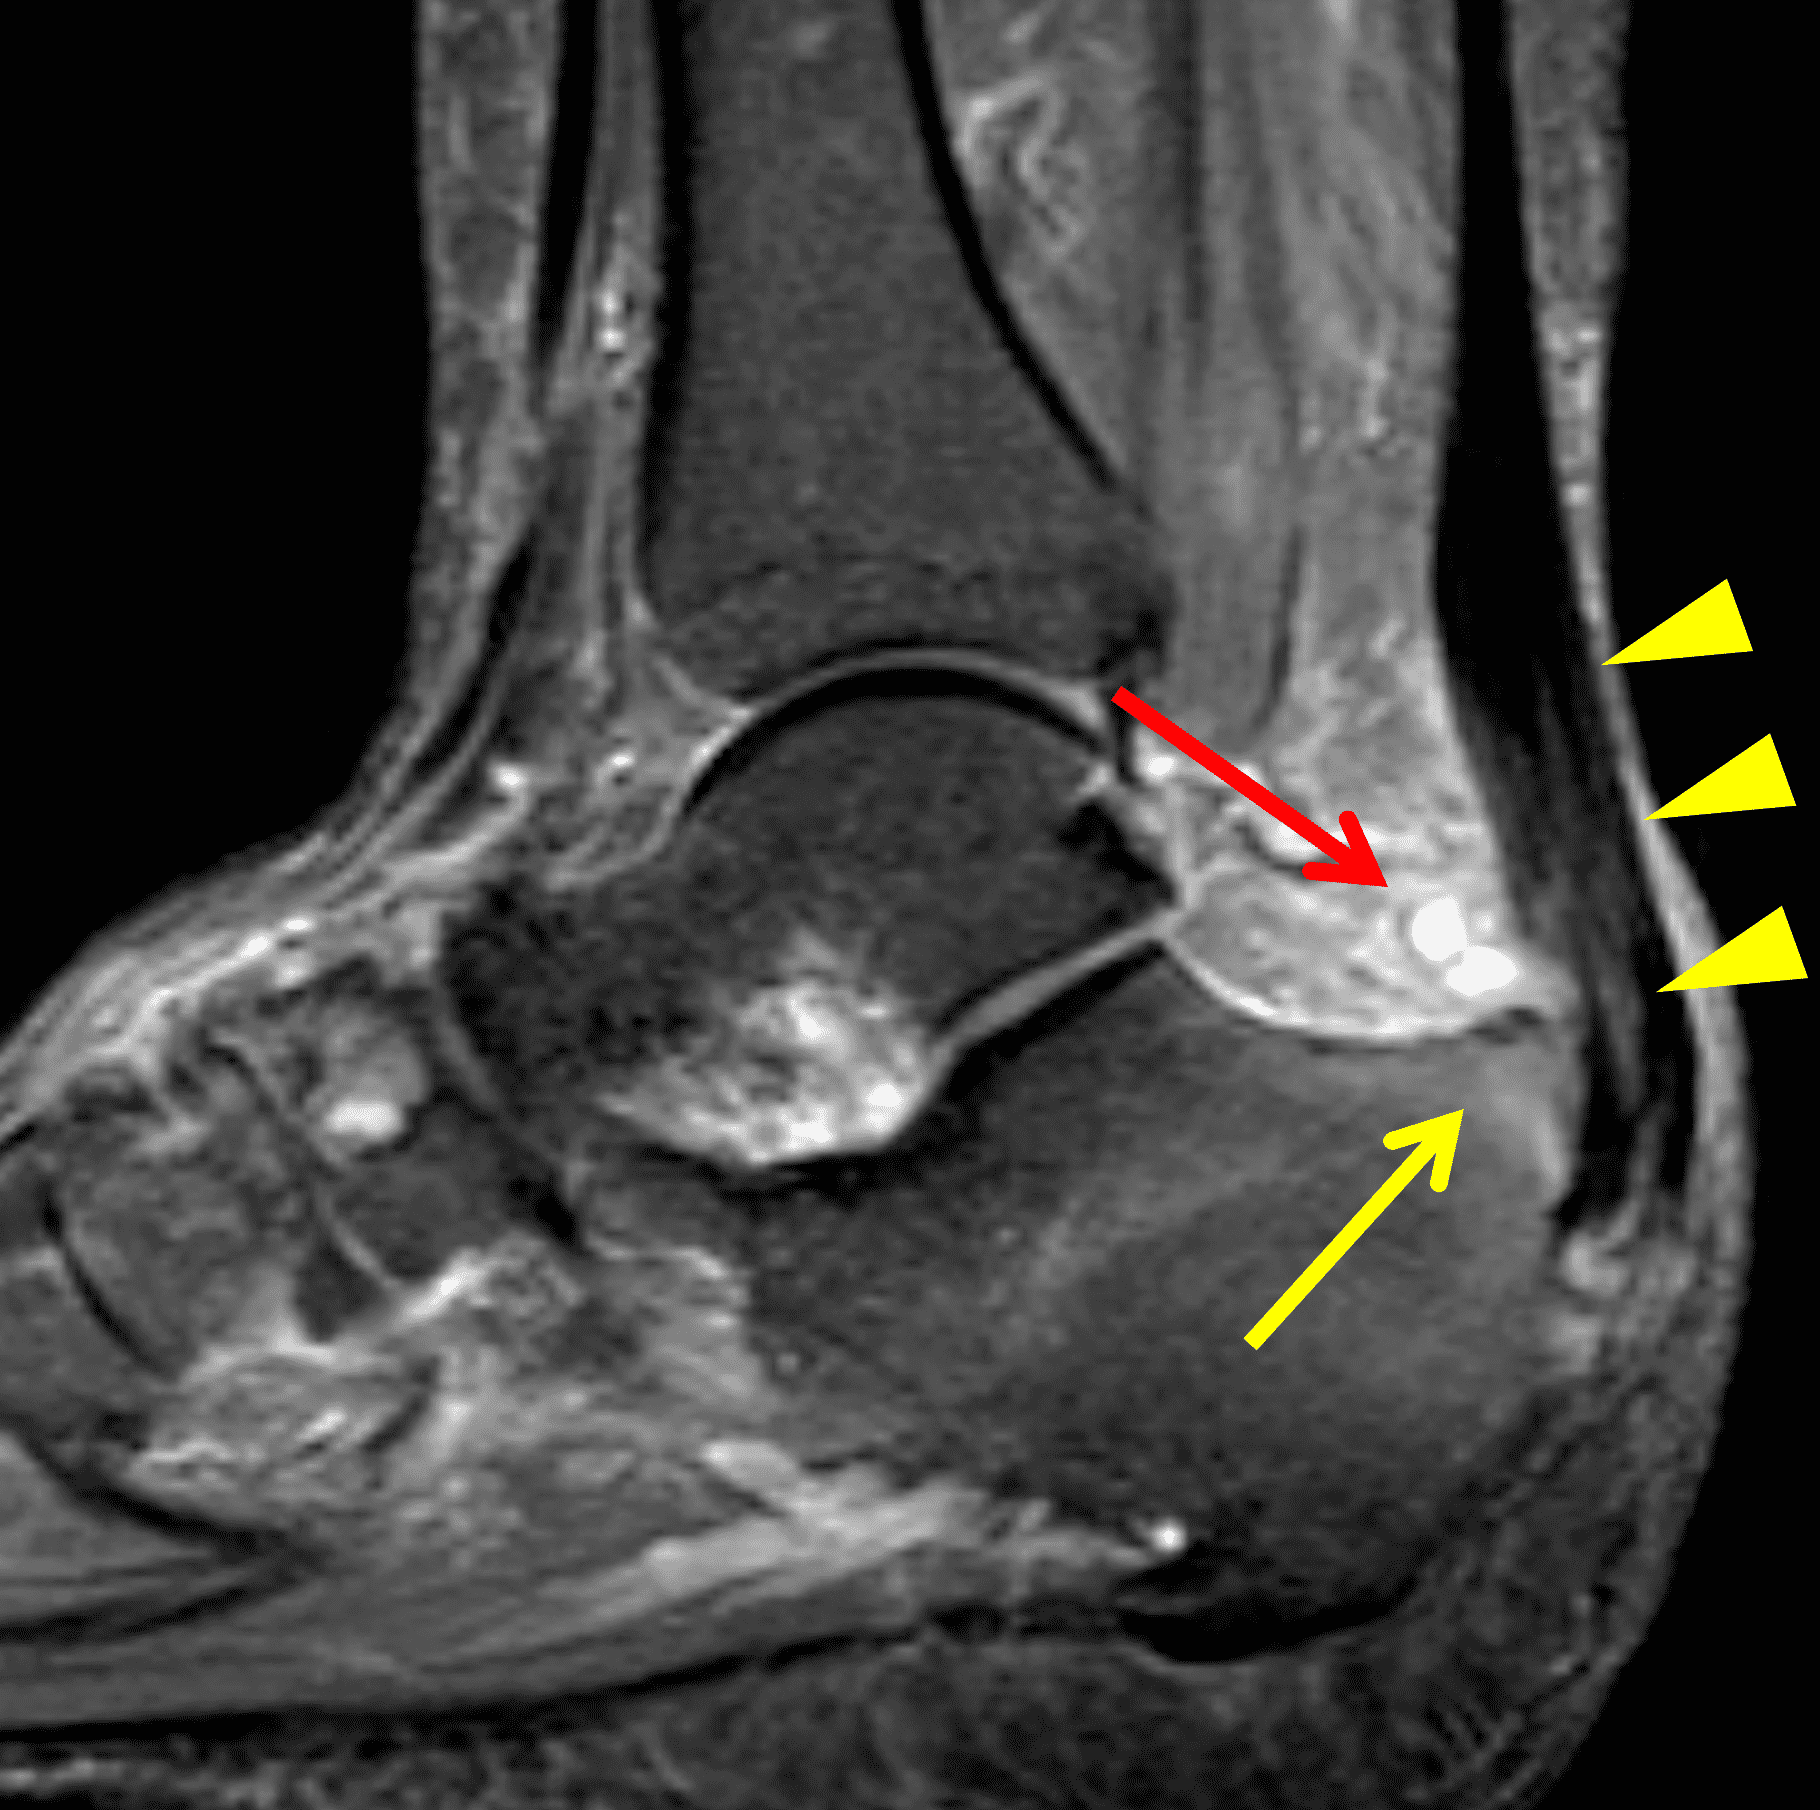

Figure 2: Complete Achilles tendon rupture. (2A) The lateral radiograph shows a thick and indistinct proximal Achilles tendon contour (arrows). (2B) A fat-suppressed T2-weighted image shows complete rupture of the tendon with a fluid-filled gap (yellow arrow) measuring 1.5 cm in length, located 10 cm cranial to the tendon insertion (blue arrow) and just distal to the edematous myotendinous junction (red arrow). The tear is superimposed on diffuse tendinosis. (2C) A sagittal T1-weighted image confirms the diffuse tendinosis. Fluid extends anteriorly into Kager’s fat pad (arrow) suggesting disruption of the anterior paratenon. (2D) A transverse fat-suppressed T2-weighted image through the proximal tendon shows no intact fibers (arrow), confirming the full-thickness rupture.